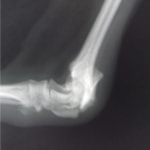

術後レントゲン